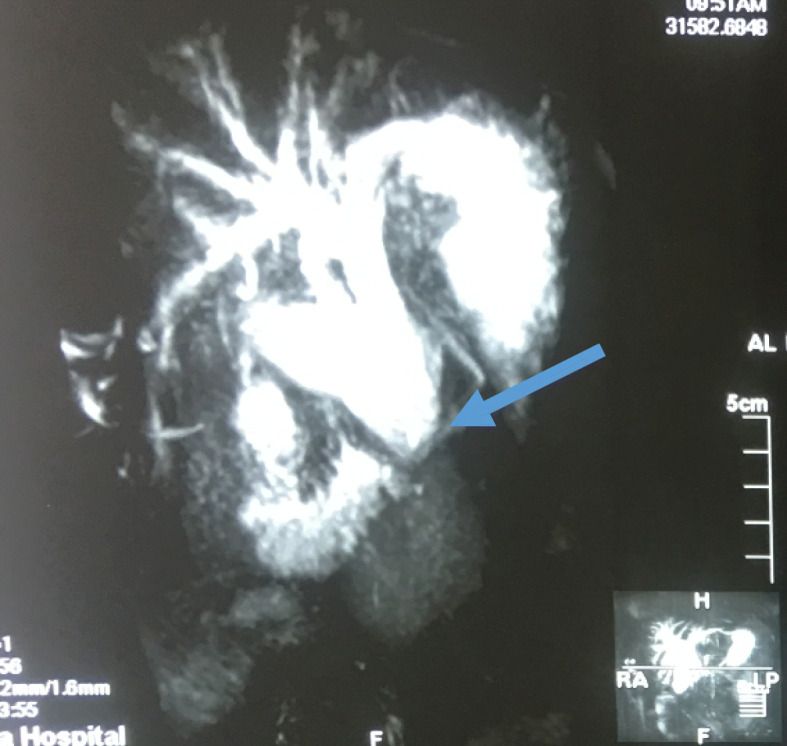

Fig. 3.

Magnetic resonance cholangiopancreatography showing dilated intrahepatic and extrahepatic biliary system down to the distal part (arrow)

Fig. 4.

Magnetic resonance cholangiopancreatography showing dilated intrahepatic and extrahepatic biliary system down to the distal part, where it is obstructed by a mass (arrow)